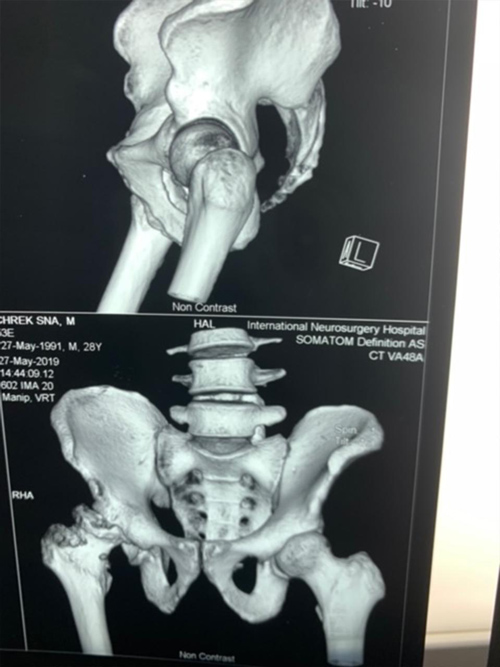

Dr. Weber and his partners participate in short term medical mission trips to Cambodia. Dr. Weber has had the pleasure of going twice now in 2018 and 2020. During these trips Dr. Weber performs total hip replacements on patients who normally would have no treatment options. To learn more and to see videos from the experience please click the links below.